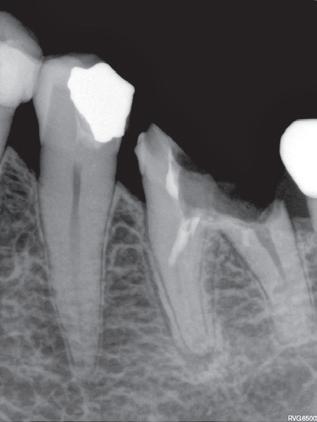

Høykonsentrert tyntflytende kalsiumhydroksidpasta med >41% hydroksid i en konsistens som enkelt appliseres med en liten og fleksibel plastkanyle: Flexi-Tip. Autoklavérbare Flexi-Tip i kombinasjon med den myke konsistensen sparer deg for tid, og hjelper deg å oppnå en presis og dyp applisering. pH 12,4 gjør den baktericid. Langvarig. Røntgenkontrast.

Calasept kalsiumhydroksid

Høykonsentrert kalsiumhydroksid på >41%. pH 12,4 gir høy antibakteriell effekt, bakteriedrepende. Røntgenkontrast. Langvarig. Klar til bruk, appliseres direkte gjennom steril kanyle.